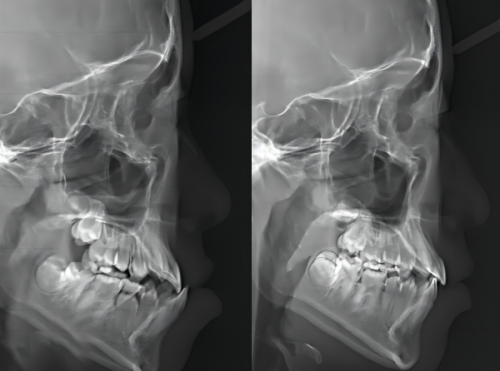

精良的设备对于口腔治疗的成效起着至关重要的作用。落后的设备可能无法正确检测出牙齿的问题,治疗过程也会相对繁琐和痛苦,这无疑增加了患者的担忧。北京京瑞口腔门诊部引进了一系列国内外精良的口腔诊疗设备,如数字化口腔全景机、激光治疗仪、隐形正畸系统等。这些设备能够快速、正确地检测出牙齿的问题,为医生的诊断和治疗提供有力的支持。同时,精良的设备也能让治疗过程更加舒适、效率高,减少患者的痛苦和治疗时间。